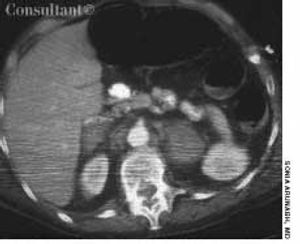

A 52-year-old woman who was undergoing chemotherapy for lymphoma was admitted to the hospital with fever of a few days' duration. The patient had smoked cigarettes for many years; she had no history of deep venous thrombosis.